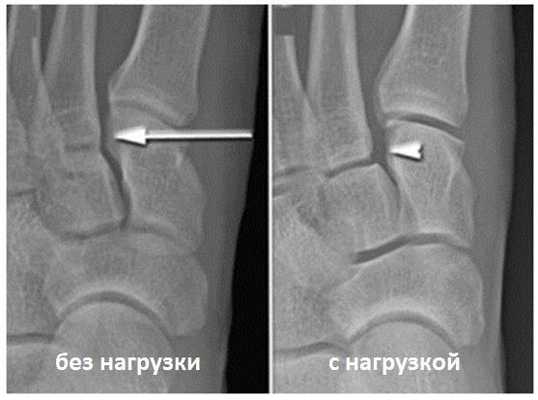

Для инструментальной диагностики используются рентгенограммы с\без нагрузки в сравнении со здоровой стороной, при их малой информативности рекомендовано выполнение стресс-рентгенограмм, аналогично приведёному выше тесту на нестабильность.

При рентгенографии все снимки выполняются в сравнении со здоровой стопой. Существует несколько основных рентгенологических признаков повреждения сустава Лисфранка. 1. Отсутствие параллельности медиального края основания 2-й плюсневой и медиального края медиальной клиновидной кости 2. Расширение между основаниями 1 и 2 плюсневых костей 3. Наличие костного фрагмента в области основания 2-1 плюсневой кости 4. Тыльный подвывих на боковой проекции 5. Разрыв линии предплюсне-плюсневого сочленения.

Вышеуказанные классификации относятся к переломовывихам, и вывихам в суставе Лисфранка, тяжёлым повреждениям, чаще встречающимся при высокоэнергетической травме, сопровождаемые значительным риском осложнений. Но во второй половине, особенно в конце XX века, в связи со значимым увеличением количества людей занимающихся спортом, возросла и частота низкоэнергетических повреждений сустава Лисфранка. В связи с чем Nunley & Vertullo в 2002 году предложили классификацию изолированных повреждений связки Лисфранка. Чаще всего они возникают при занятиях спортом и других низкоэнергетических травмах, и затрагивают только среднюю колонну стопы - 2-3 предплюсне-плюсневые суставы. Диагностика этих повреждений крайне сложна, так как рентгенологические признаки выявляются только при выполнении рентгенограмм с нагрузкой. Тем не менее это важная ортопедическая задача, так как повреждения 2-3 ст если оставить их не леченными часто приводят в последующем к хроническим болям в стопе и значительному ограничению уровня физической активности.

Отдельно стоит разобрать тему разрыва связки Лисфранка с изолированной нестабильностью 2 предплюсне-плюсневого сустава. Частота данного повреждения значительно выросла за последние 50 лет в связи с популяризацией спорта. Также крайне высота частота отсроченной постановки диагноза. При этой патологии пациента беспокоит боль по тыльной поверхности 1-2-3 предплюсне-плюсневых суставов при физической нагрузке. Часто при осмотре удаётся обнаружить деформацию в данной области. Если осмотр производится отсрочено через несколько недель или месяцев после травмы то клинически определить нестабильность уже не удастся, однако на рентгенограммах с нагрузкой будет виден диастаз между медиальной клиновидной костью и основанием 2 плюсневой кости.